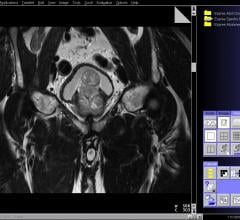

February 18, 2015 — Sonus Imaging developed a new, advanced ultrasound system for magnetic resonance imaging (MRI) ...

February 3, 2015 — Targeted biopsy using new fusion technology that combines magnetic resonance imaging (MRI) with ...

January 13, 2015 — A new novel imaging technique measurably improves upon current prostate imaging and may have ...

December 4, 2014 — Chesapeake Urology Associates offers a state-of-the-art prostate cancer diagnostic, which fuses ...